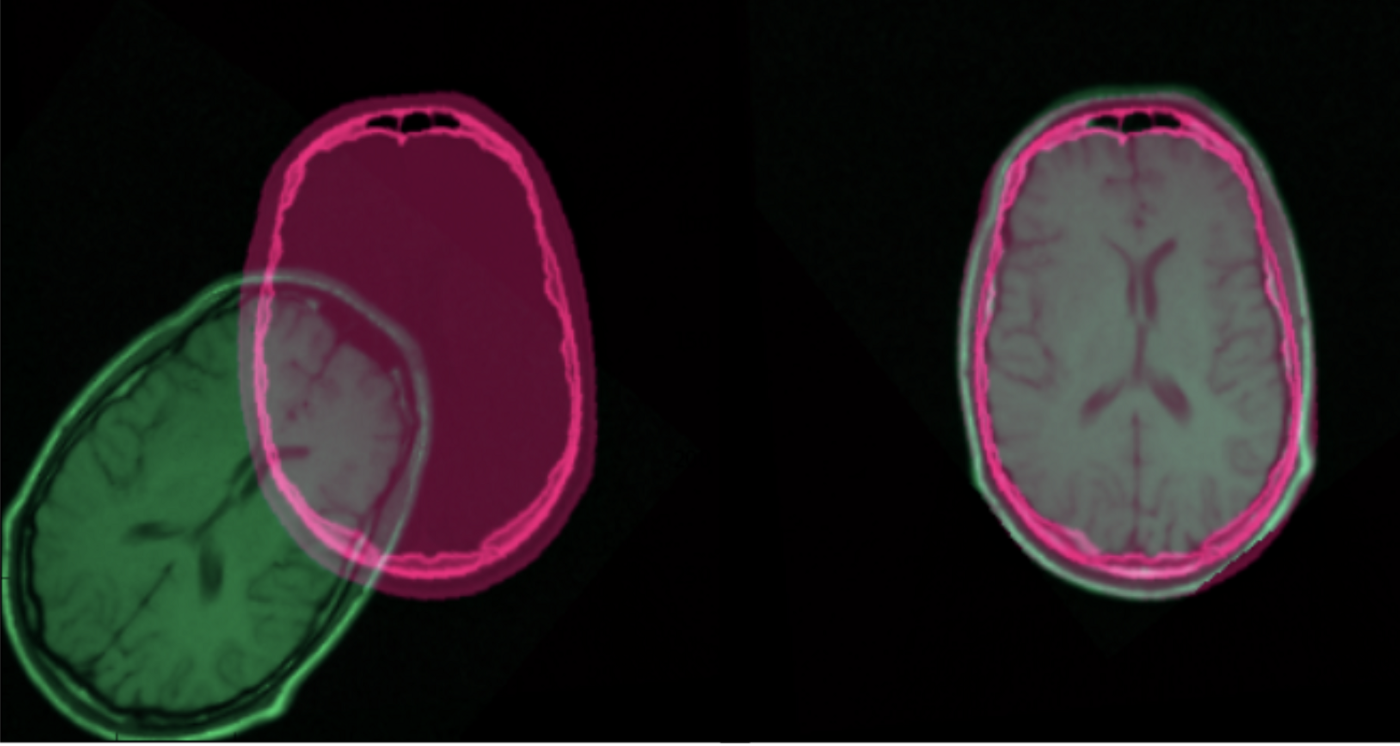

Segmentation

Registration